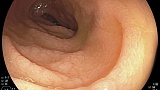

Пациент, ж, 20 лет, направлен терапевтом на ЭГДС с жалобами на вздутие живота, длительной диареи, потеря массы тела.

При осмотре луковицы ДПК отмечается ячеистый рисунок слизистой, сглаженность складок. При увеличительной узкоспетральной эндоскопии сглаженность и потеря ворсинчатой структуры слизистой (атрофия). Гистологически - стадия Marsh 3B.